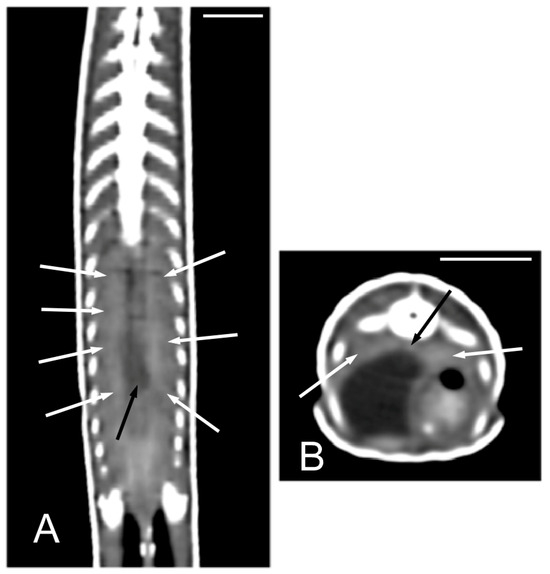

The kidneys and ovaries were identified only in postcontrast CT images. The kidneys appeared as a pair of soft tissue attenuating elongated structures in a ventrolateral position to the spine, in the caudal third of the coelomic cavity. They were best seen in the transverse and dorsal planes. Their margins were not well defined. The aorta was only seen in the midline between them (Figure 13). We could distinguish ovarian follicles only in one individual and they appeared as hypoattenuating rounded to oval structures, bounded by fine slightly hyperattenuating margins (Figure 14). The ureters, urinary bladder, oviducts, testes, and hemipenes were not recognizable in our CT studies.

Figure 13.

The postcontrast CT images of Pseudopus apodus in the dorsal (A) and transverse (B) planes showing both kidneys (white arrows) and the aorta (black arrow) between them in the dorsal part of the coelomic cavity, just ventral to the spine. Bar = 10 mm.

In our case, only the kidneys were identified between the urinary organs. They were best seen in postcontrast images in transverse and dorsal planes, using the spine as an anatomic landmark. Being paired organs makes their identification easier. In the study by Banzato et al. [34], who obtained only postcontrast CT images, the renal parenchyma showed an in-homogeneous appearance in the green iguanas and common black and white tegus, while it appeared quite homogeneous in bearded dragons. Sochorcová et al. [37] reported that in contrast-enhanced CT of red-eared terrapins, the maximum contrast enhancement of the kidneys was detected 20 s after the contrast injection; the kidneys showed a homogeneous contrast enhancement, and the ureters could be clearly identified in postcontrast images of this reptile. In the CT study performed by Melero et al. [42], carried out in chameleons, the kidneys appeared as lobulated, oval, bilateral and symmetric structures, with soft tissue attenuation. They were more easily identified in the postcontrast studies and sagittal plane, showing a diffuse heterogeneous contrast enhancement. In our study, the kidneys showed homogeneous enhancement after contrast administration, and they were best identified in transverse and dorsal planes. The ureters could not be identified in chameleons [42], which is the same as in our study. The urinary bladder could not be observed during the study of [34] the green iguana, the common black and white tegus, and the bearded dragon; it is easy to identify in red-eared terrapins [37], whereas in chameleons, it was visualized in pre and postcontrast studies only in animals that presented with hyperattenuating urate salts in the lumen [42].